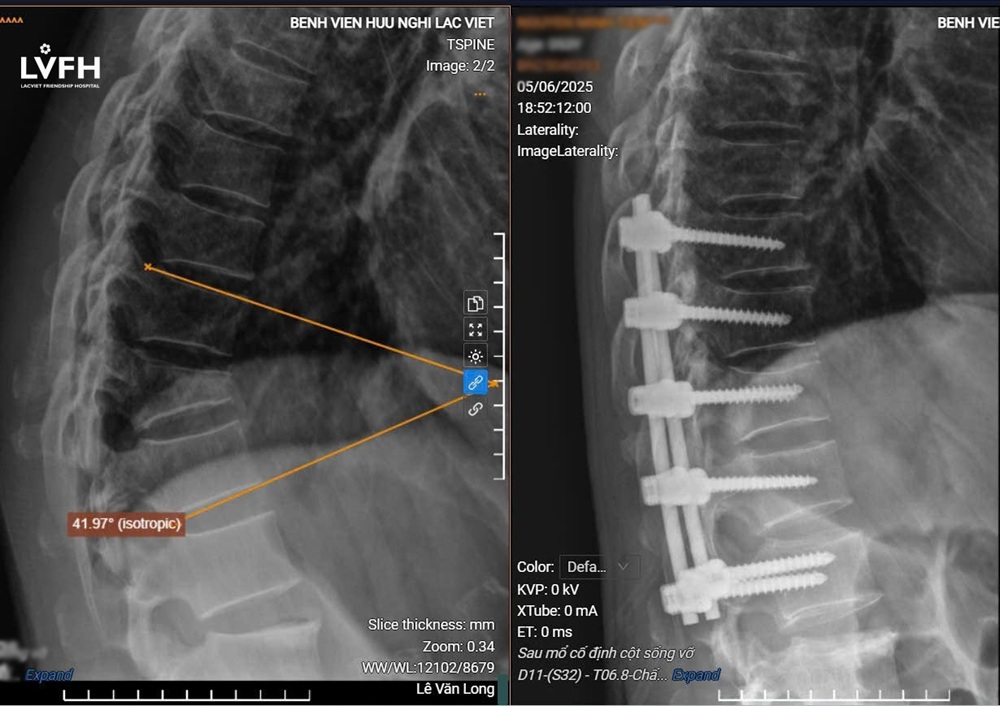

Kết quả chụp X-quang cho thấy, bệnh nhân bị gù cột sống ngực với góc gù vùng lên đến 42 độ. Sau khi hội chẩn và tư vấn kỹ lưỡng cho bệnh nhân và gia đình, ekip phẫu thuật do ThS.BS Lê Văn Long – Phó Trưởng khoa Ngoại 2, Bệnh viện Hữu nghị Lạc Việt trực tiếp thực hiện đã tiến hành ca phẫu thuật nắn chỉnh gù cột sống.

Sau mổ, cột sống bệnh nhân đã thẳng trở lại, giảm đau rõ rệt và có thể sinh hoạt bình thường.